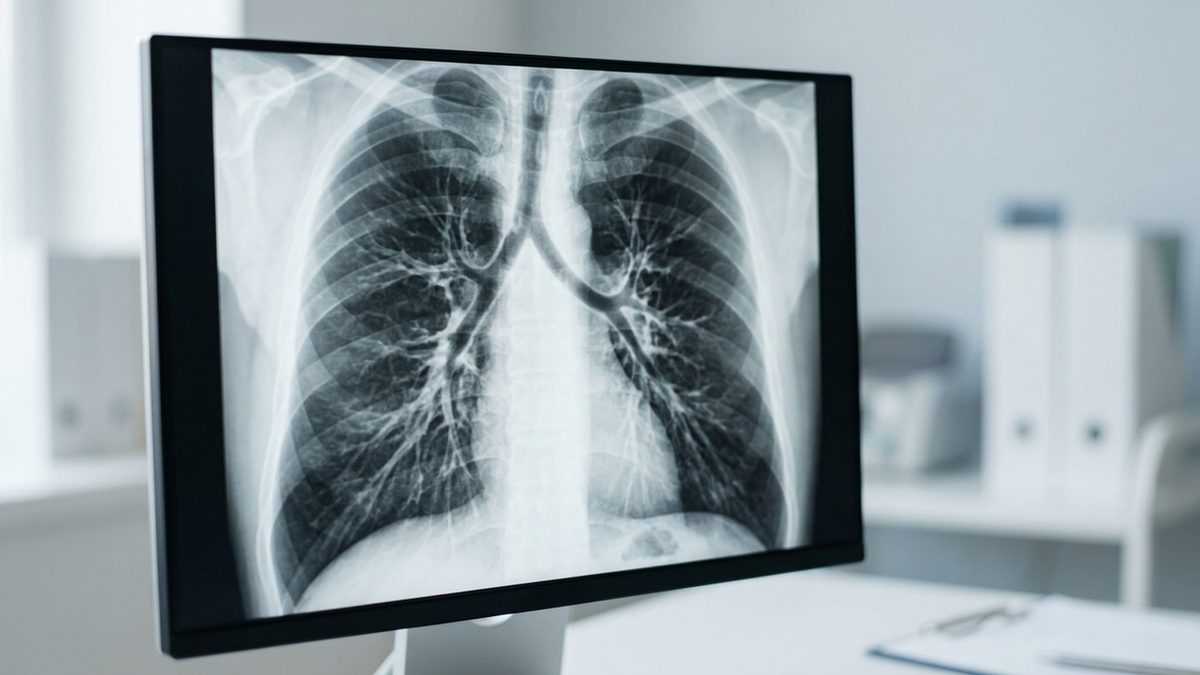

التهاب الشعب الهوائية قد يكون حاداً بفعل الفيروسات وقابلاً للشفاء، أو مزمناً بسبب الملوثات والأدخنة. الأعراض تشمل السعال المتكرر وصعوبة التنفس، بينما الوقاية تبدأ بجودة الهواء واللقاحات الموسمية.